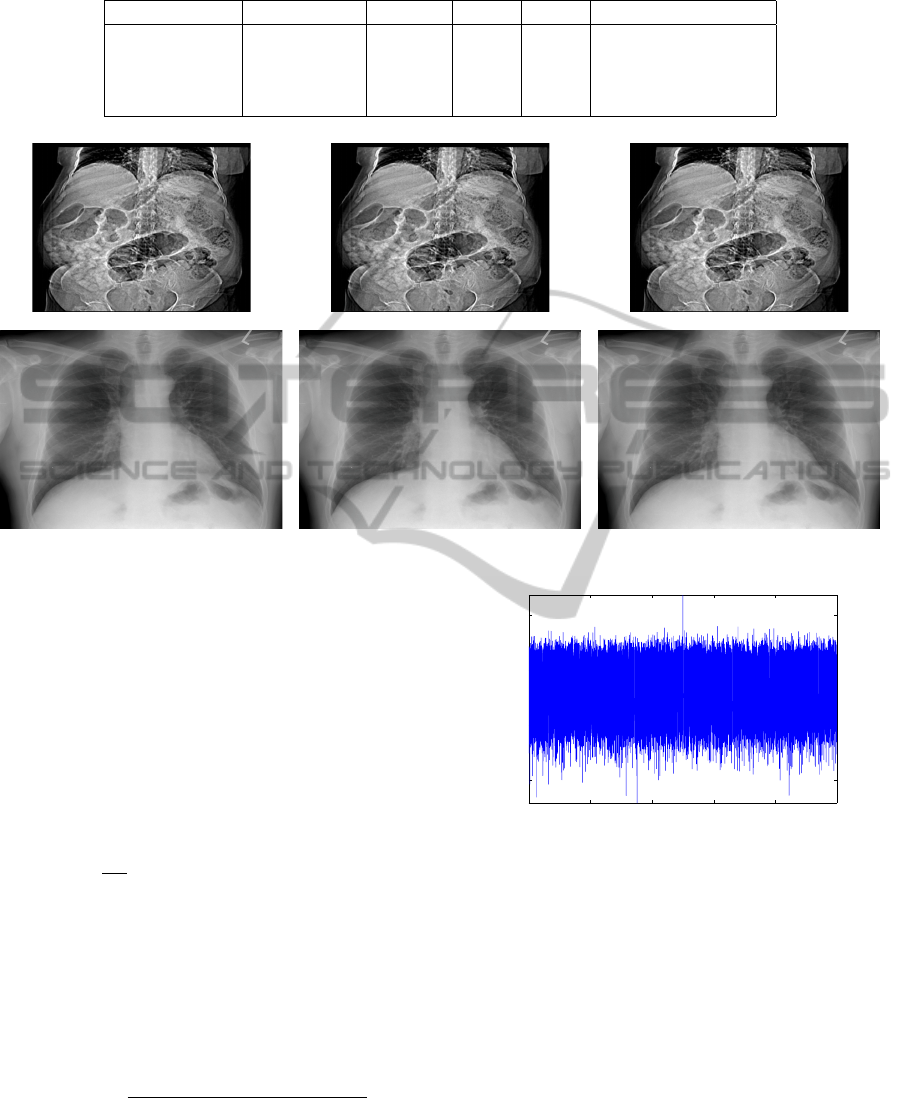

The proposed algorithm involves encryption of

Golomb coded bit stream while embedding water-

mark through context. Encryption is performed on the

output bit stream of JPEG-LS compression (figure 1-

a). The encryption algorithm that we propose to use

is RC4 cipher (Schneier, 1996). The encryption does

not result in any increase in compressed file size as

the encryption is done using a stream cipher. The en-

crypted bit stream along with classmap f and context

frequencies is sent to the watermark embedder (figure

1-b) where the watermark embedding takes place.